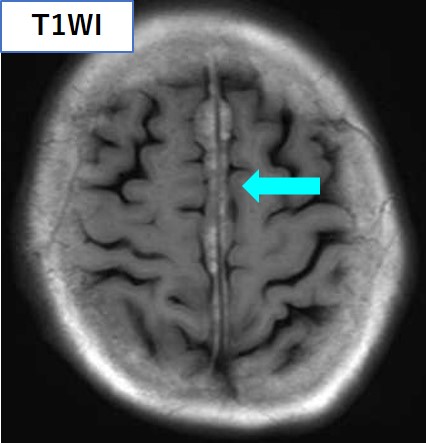

頭部CT・MRIにて、大脳鎌に沿った腫瘤を認め、左小脳橋角部にも腫瘤を認める。いずれもT1強調像で高信号、T2強調像で低信号を呈している。

頭部MRI

<中枢神経病変>

• 髄膜に沿った腫瘤形成(23%)

• 下垂体後葉のT1高信号が消失(47%)